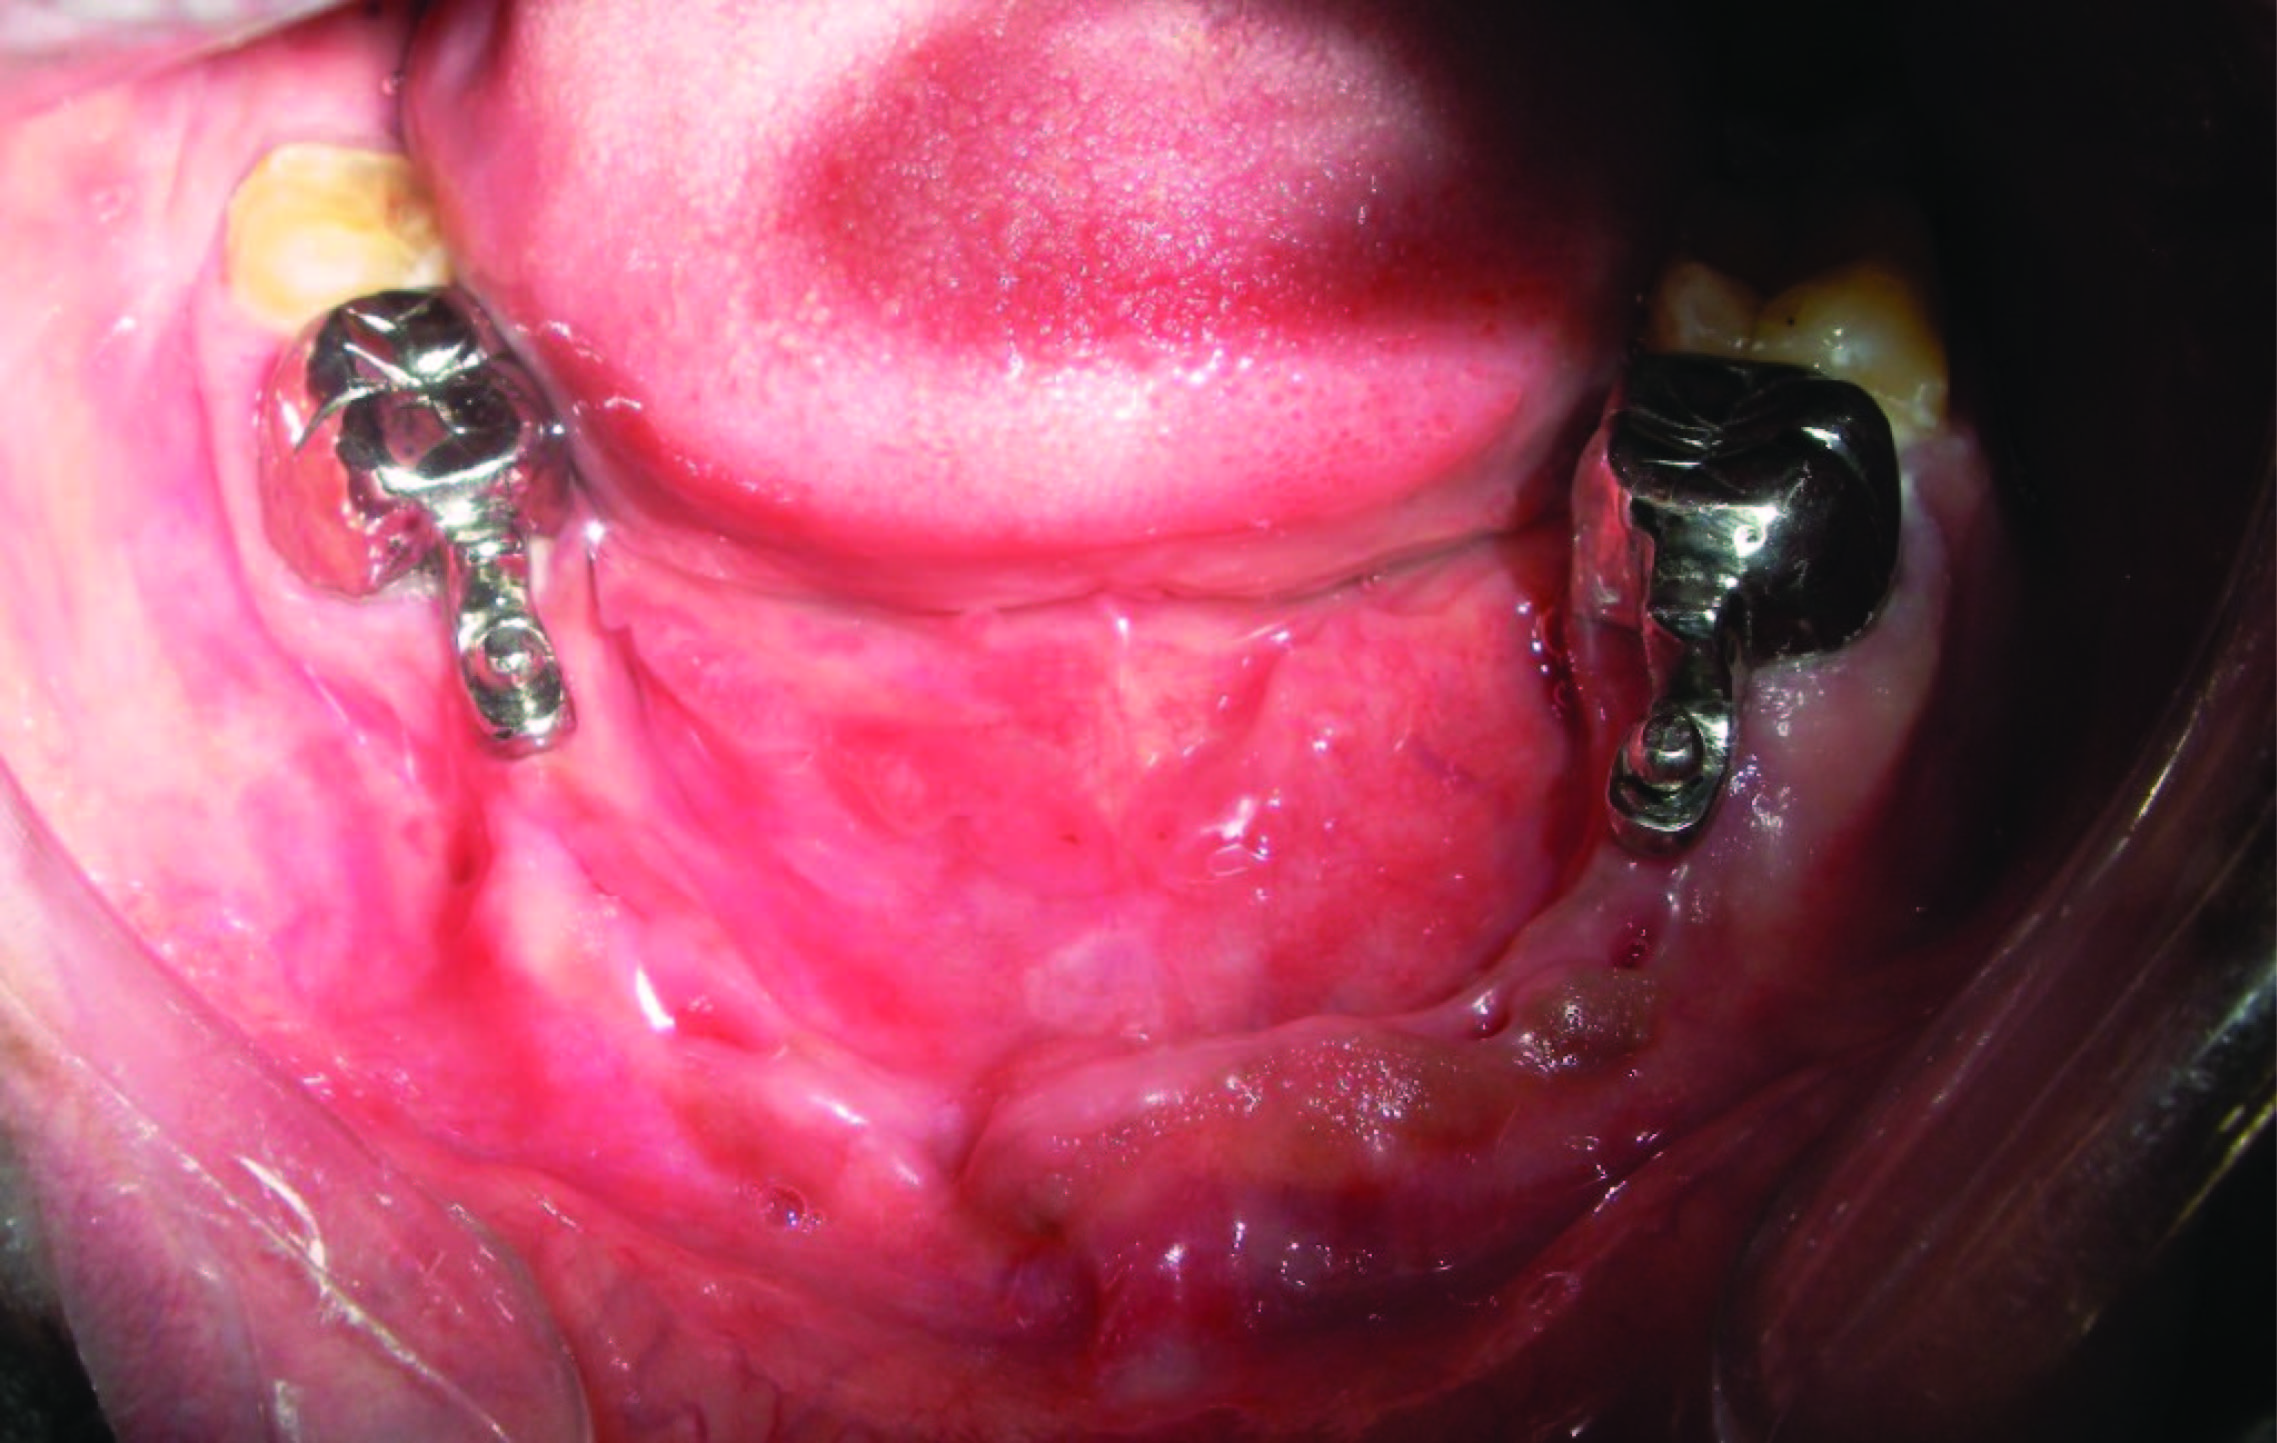

Trial seating of the finished prosthesis was performed. retentive caps were placed on top of ball attachments [Table/Fig-3]. These retentive caps were picked up within the partial denture with the help of self cure acrylic resin (DPI, cold cure) [Table/Fig-4]. After the final insertion [Table/Fig-5&6] routine oral hygiene instructions were given.

Full metal crown along with retentive resilient cap in 47&36